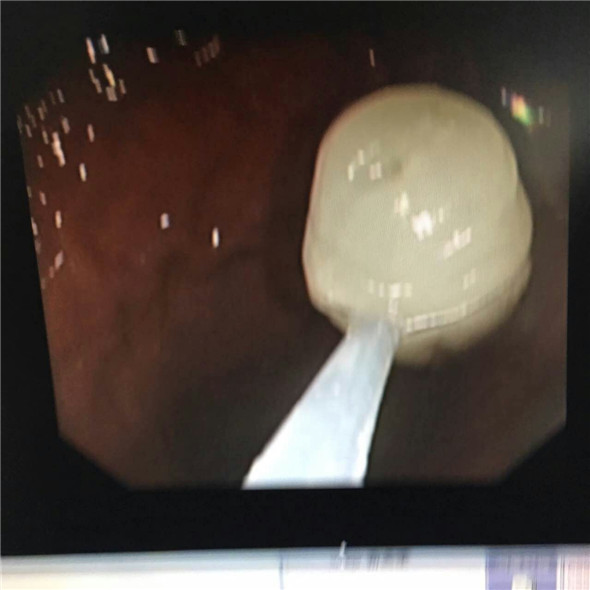

在手术的开始王主任尝试用异物钳取物,但是玉石太光滑很难抓住,后改用圈套器,试了几次石块都会从钢丝内脱落。30分钟的时间过去,患者已经开始躁动不安了。王主任冷静应对用石网篮取石,网蓝的四线钢丝应该比两线的圈套器抓取的更牢固,经过尝试果然见效,石块抓住了,但也只是抓住了石块尾部很难完整拖出,遂即又向食道内下滑管,不断旋镜调整角度,最后,借助滑管的扩张力将玉石取出。一般来说胃镜取物术只需要20分钟,但是这次手术却花费了一个小时,主治医生的脸上早就布满汗水,护士的手腕也被患者握出紫痕。好在经过手术,患者已经可以安然出院了。

玉坠从胃中取出过程